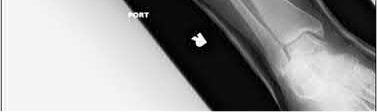

A 64-year-old woman is thrown off a horse, sustaining the injury shown in Figures A and B. She undergoes surgical fixation as seen in Figures C through E. What is the most commonly reported complication of this procedure?

The patient in the scenario has a 2-part proximal humerus fracture treated with a locking plate as seen in Figures A-E. The most common complication with the use of this implant is screw penetration. The terms screw cut out and penetration are often used interchangeably in the literature with cut out appearing more frequently in reports regarding intertrochanteric fractures.

Owsley et al retrospectively reviewed 53 proximal humerus fractures treated with locking plates and the same post-operative protocol. The most common complication was screw cut out or penetration, followed by varus displacement. They concluded that 3 and 4-part fractures in patients over 60 years have a higher incidence of failure.

Agudelo et al retrospectively reviewed 153 patients at a level-one trauma center treated with proximal humerus locking plates, investigating modes of failure for the implant. They determined that varus malreduction (head-shaft angle